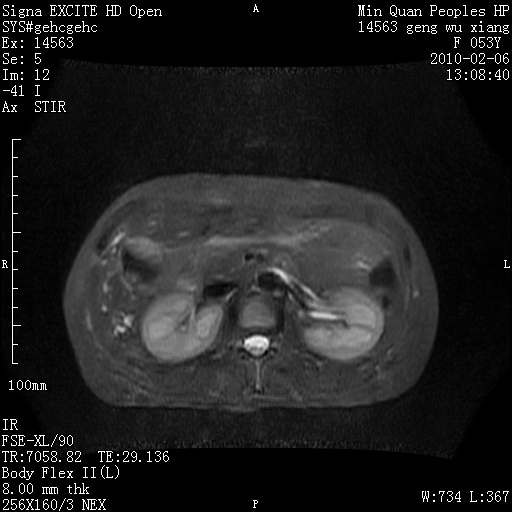

标题: MRI2762:胆道梗阻原因?

f,53y,全身黄染多日。

高位胆道梗阻 胆管癌可能性大

支持 高位胆道梗阻 胆管癌可能性大。